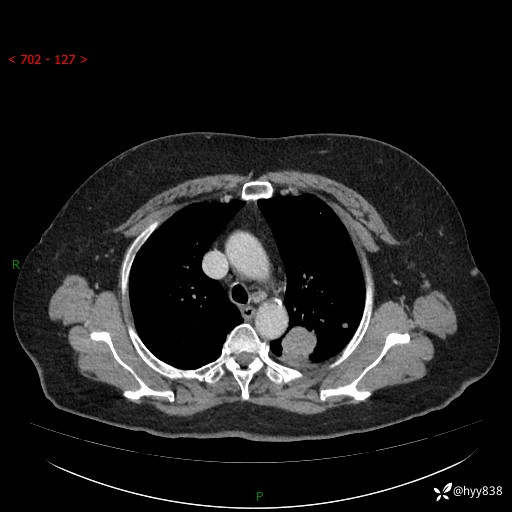

老年女性,左上肺结节8年。典型又不典型,看你如何解读---结果公布(值得分析)

主诉:检查发现左上肺结节8年,较前增大。

简要病史:患者于8年前体检行胸部CT检查发现左上肺结节(4mm),患者平素间断咳嗽咳痰,无心慌、胸闷、胸痛、呼吸困难、低热、盗汗,无头痛、头晕,无腹痛、腹胀等不适,未行特殊处理,定期复查。2023-09-21胸部CT示左上肺结节(2cm)较前增大,2024-02-01胸部CT示左上肺尖后段(39*32mm),左侧肺门及纵隔淋巴结增大,现患者欲求手术治疗,遂来我院就诊,以“左上肺结节”收入我科。 患者自起病以来,精神可,睡眠可,饮食可,大小便正常,体重无明显改变。

辅助检查:CT

胸部CT平扫

增强(动脉期+静脉期)